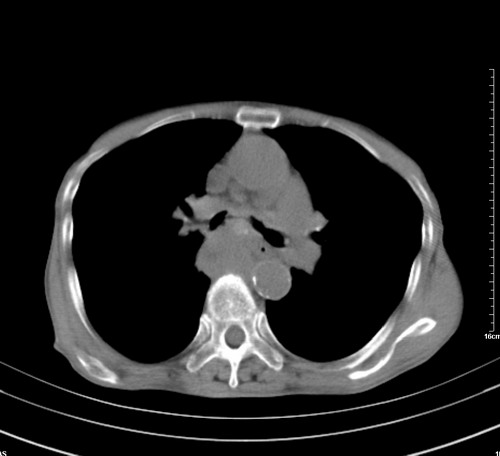

中后纵隔占位,气管、食道受压、变形、移位。恶性可能性大。

考虑:中后纵隔转移瘤可能性大,主动脉硬化。

中后纵隔占位, 考虑:转移瘤不除外.

1 气管旁、隆突下淋巴结明显肿大,肝左叶外侧段低密影,都考虑转移。

纵隔淋巴结肿大,考虑转移而来

肺癌,纵隔淋巴结转移,肝左叶病变考虑为转移病灶。

中后纵隔转移瘤可能性大,主动脉硬化。

中后纵隔转移瘤可能性大

后中纵隔团块影,伴气管、食道受压移位,首先考虑转移瘤,肝s5段低密度灶。建议增强检查,另外其结肠是否有问题请提供,右肺部分肺叶局限含气增多,考虑局限肺气肿。

建议强化检查,考虑纵隔型肺癌,小细胞可能性大。

后中纵隔团块影,伴气管、食道受压移位,首先考虑转移瘤,肝表现同11773。

后中纵隔淋巴结肿大,首先考虑转移瘤。